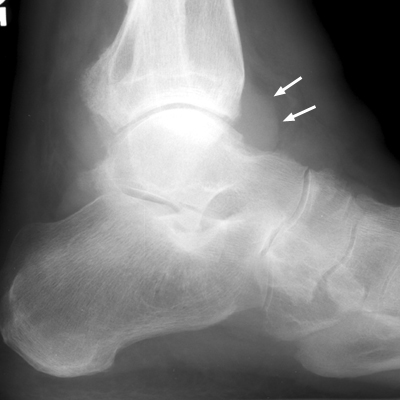

Diagnosis:Ankle effusion Discussion:One normal ankle radiograph (A), and one abnormal ankle radiograph (B) revealing a moderate effusion. The teardrop shaped density seen extending anteriorly from the ankle joint along the neck of the talus has been referred to as the "teardrop sign" of ankle effusion. This is a useful sign in the diagnosis of ankle joint effusion, and may alert the diagnostician to possible underlying pathology. References: